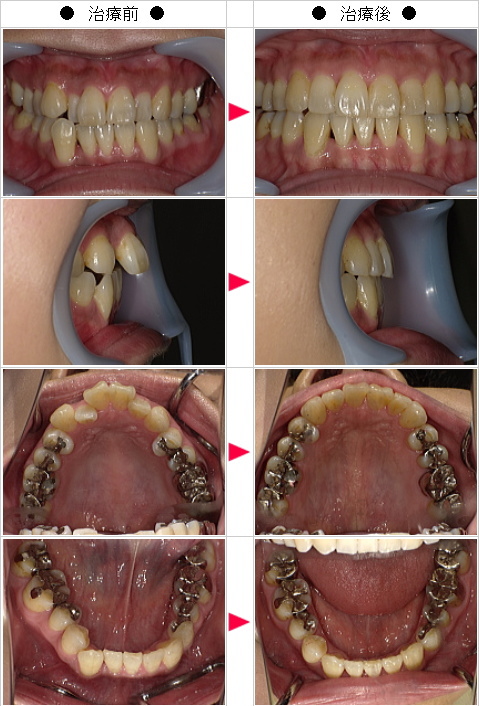

☆出っ歯矯正の治療症例[S・N様 40歳 女性]